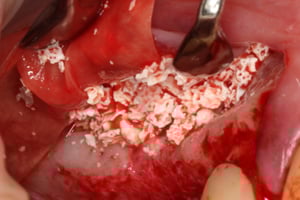

W każdej z metod, po odwarstwieniu błony Schneidera (błony śluzowej wyścielającej ściany zatoki), w wytworzoną przestrzeń wprowadzany jest materiał kościozastępczy będący zrębem dla powstawania nowej tkanki kostnej.